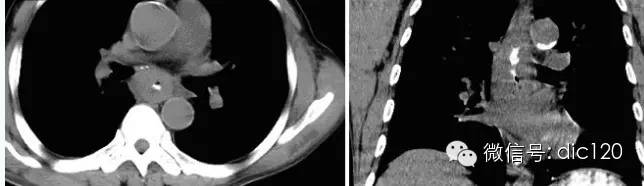

① CT檢查可清晰地顯示食管壁與鄰近或周圍器官(如縱隔、氣管、支氣管、心包、肝臟等) 的關系,并可測量食管壁的厚度。正常食管厚度不超過5mm,若食管壁厚度 >5.0mm,常提示有局部病變的可能,因為發生食管癌時,管壁成環形或不規則增厚。

② CT檢查還可充分顯示食管癌病灶大小、腫瘤外侵范圍及程度,對腫瘤的分類、分期、術前判斷手術切除的可能性、預后的評估均有幫助。

③ CT是發現食管癌轉移的最佳影像方法。腫瘤可引起氣管支氣管的移化、變形,若同時伴有管腔狹窄、管壁腫脹,特別是呈不規則形時,應高度懷疑惡性病變。但CT掃描所見并不能鑒別正常體積的淋巴結有無轉移,腫大的淋巴結是否由炎癥或是腫瘤轉移所致,對直徑<1cm的轉移淋巴結更易被遺漏。